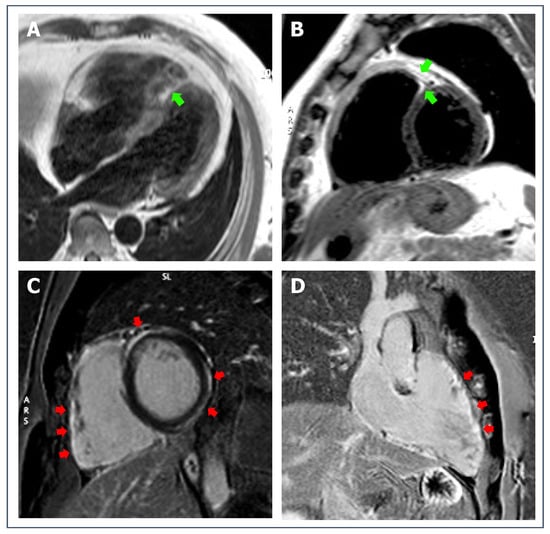

- Muser, D.; Nucifora, G.; Muser, D.; Nucifora, G.; Pieroni, M.; Castro, S.A.; Arroyo, R.C.; Maeda, S.; Benhayon, D.A.; Liuba, I.; et al. Prognostic value of nonischemic ringlike left ventricular scar in patients with apparently idiopathic nonsustained ventricular arrhythmias. Circulation 2021, 143, 1359–1373. [Google Scholar] [CrossRef] [PubMed]

- De Lazzari, M.; Zorzi, A.; Cipriani, A.; Susana, A.; Mastella, G.; Rizzo, A.; Rigato, I.; Bauce, B.; Giorgi, B.; Lacognata, C.; et al. Relationship between electrocardiographic findings and cardiac magnetic resonance phenotypes in arrhythmogenic cardiomyopathy. J. Am. Heart Assoc. 2018, 7, e009855. [Google Scholar] [CrossRef] [PubMed]